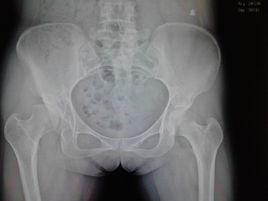

如果你注意到寶寶出現以上任何問題,要及時帶他去醫院檢查。醫生不僅通過體格檢查來診斷髖關節發育不良,還可能會藉助B超、X光來觀察髖關節的發育情況,以便儘早發現寶寶是否存在問題。